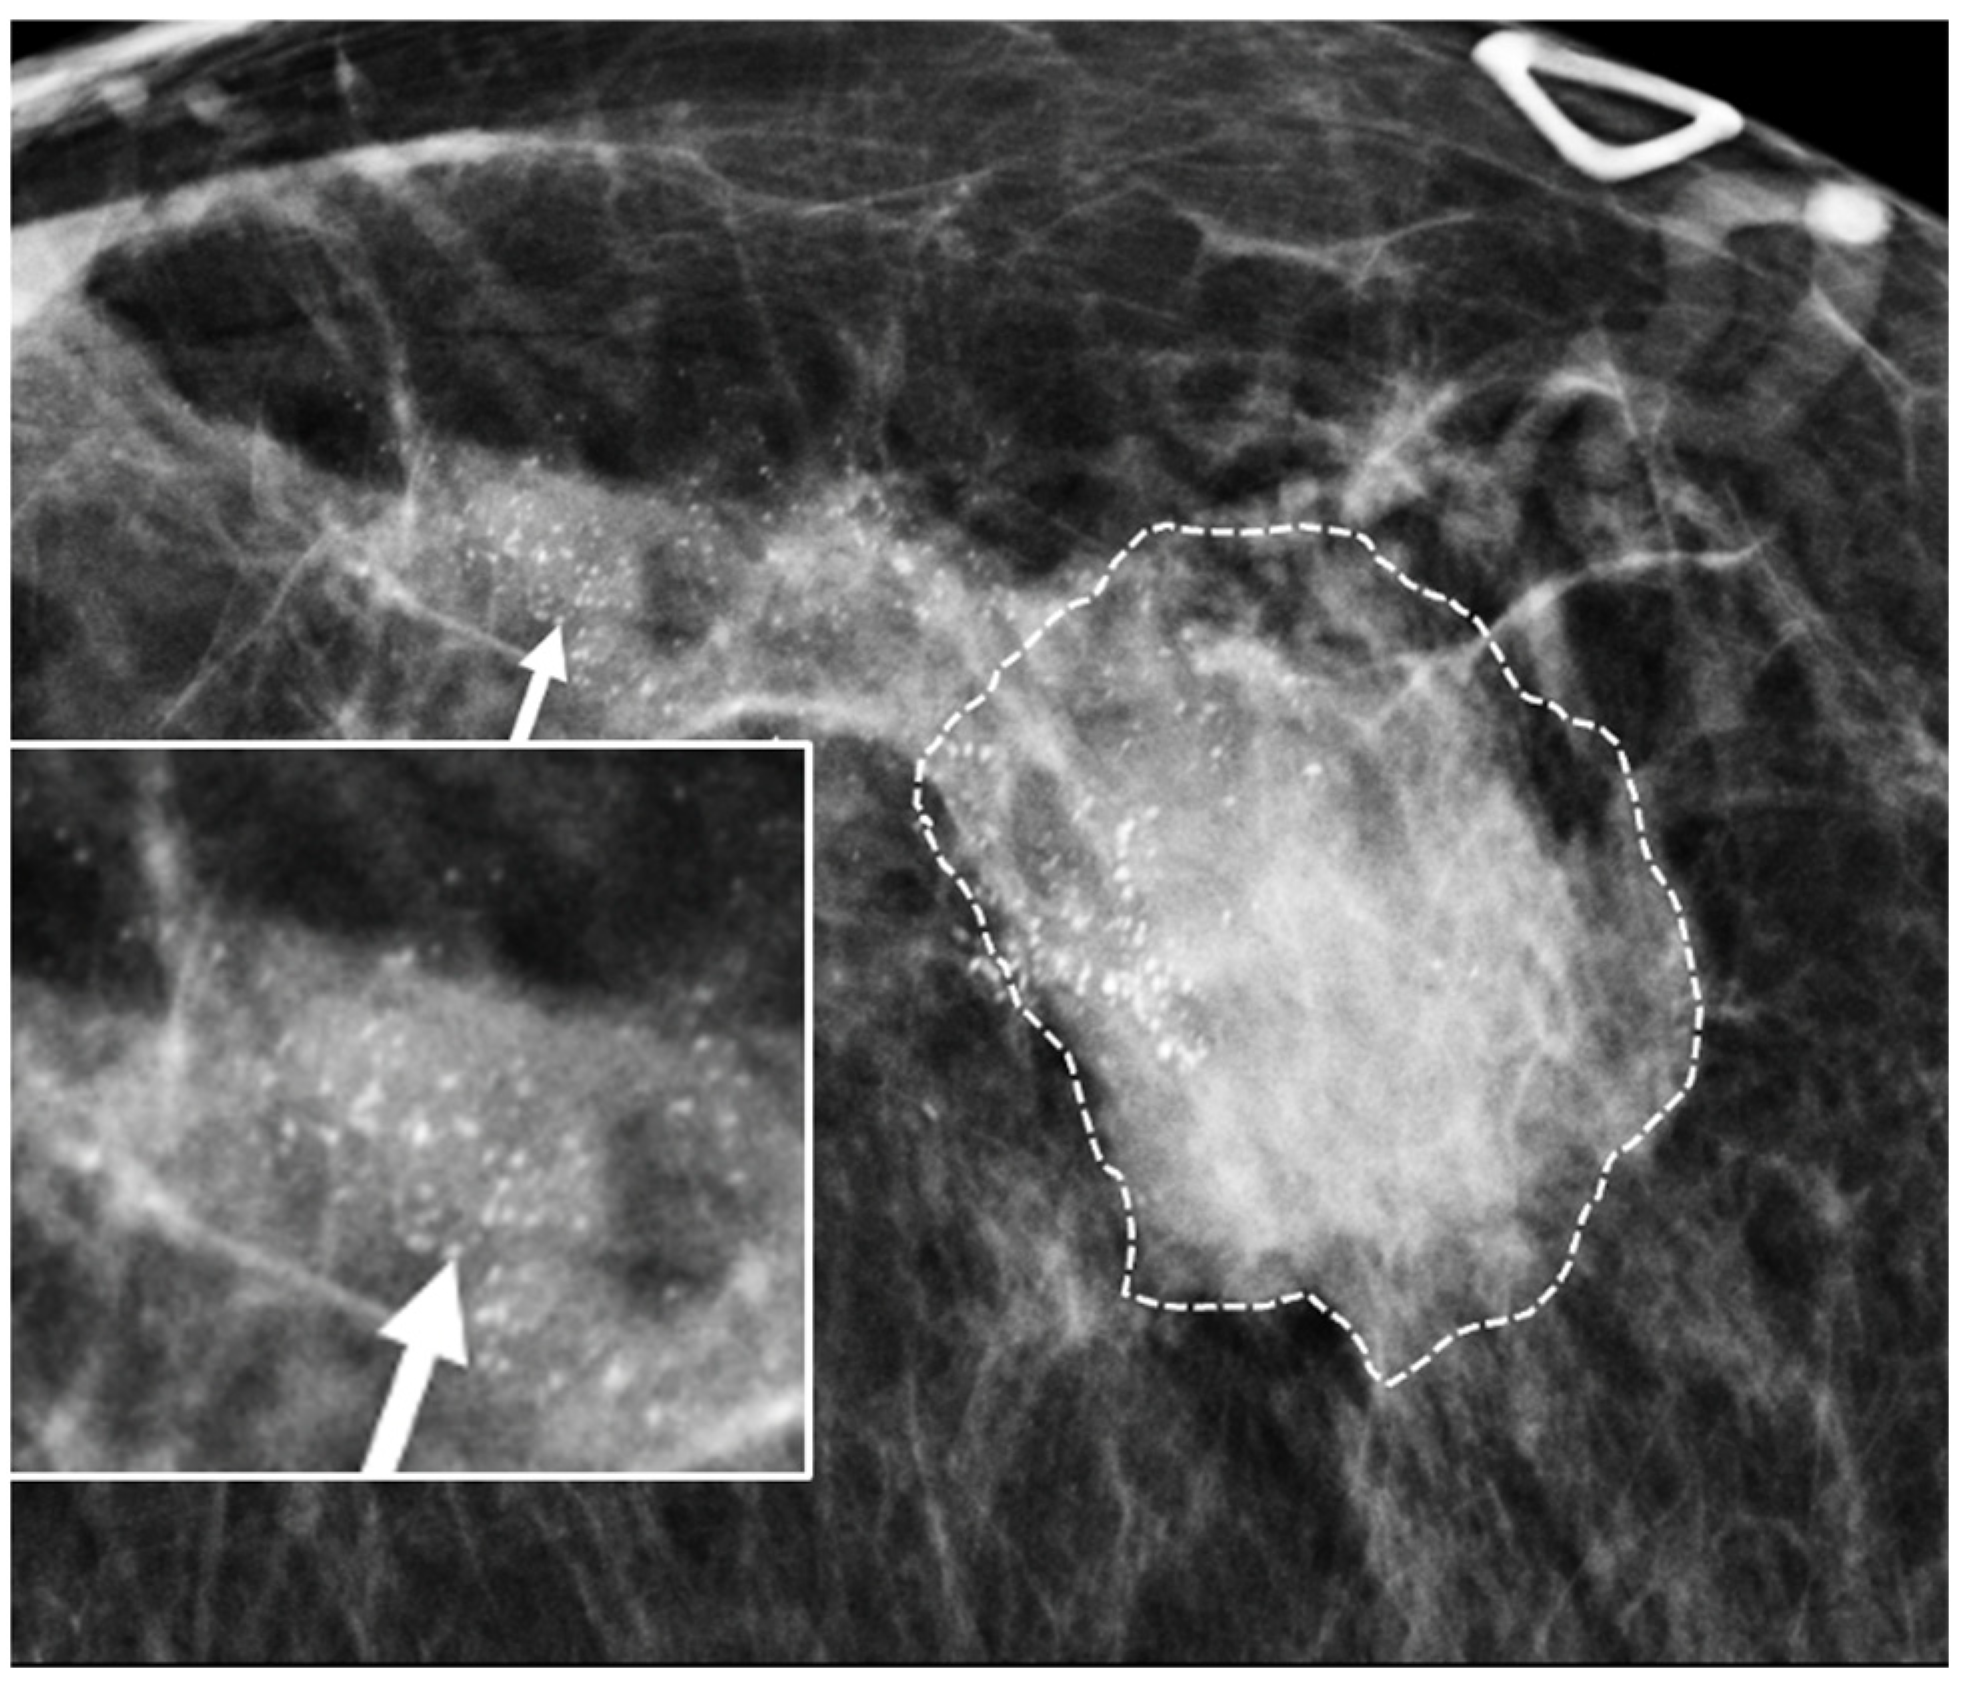

Digital Mammography. Breast cancer staging should include bilateral digital diagnostic mammograms (preferably 3D mammograms or tomosynthesis) to evaluate the extent of disease. Although cryoablation is generally performed under ultrasound or CT-scan guidance, high-quality mammography might reveal additional areas of cancer in the same region of the breast (multifocal cancer) or in a different region of the breast (multicentric cancer) that might impact patient selection or alter the cryoablation treatment plan. Multicentric and multifocal breast cancer is generally regarded as a contraindication to cryoablation. Pre-treatment assessment of the mammograms should seek the detection of spiculations (radial tumor extensions) and/or microcalcifications that might reach beyond the main tumor mass and require incorporation in the cryoablation treatment zone (Figure 1). Since mammography is the only imaging study that reliably shows microcalcifications, mammography plays a particularly important role in determining disease extent when suspicious microcalcifications are part of the disease process. Consequently, patients who are generally opposed to obtaining screening mammograms should be encouraged to have at least one set of pre-treatment diagnostic mammograms to exclude the presence of suspicious microcalcifications that could impact patient selection and/or treatment planning.

Figure 1.

Mammogram showing density corresponding to a palpable mass (see dashed lines) as well as suspicious microcalcifications (arrows) and inset image showing magnified view of white punctate calcifications extending beyond the palpable mass.